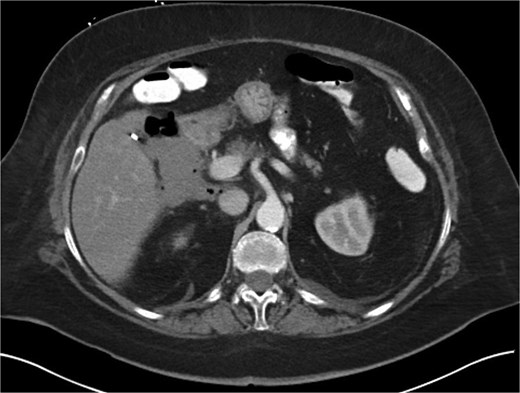

A 70-year-old woman with obesity, non-insulin-dependent diabetes, gastroesophageal reflux disease (GERD), cholecystectomy, and prior RYGB presented to the ED with acute chest and lower abdominal pain. The pain began 1 day earlier and initially responded to Ibuprofen, which she had been taking 4–6 times daily for musculoskeletal discomfort. Her pain worsened, radiating to her back, and was accompanied by belching and vomiting with dry heaving. She denied trauma or changes in bowel habits. Initial CT (Fig. 1) imaging showed a moderate hyperdense area around the duodenum, distension of the afferent limb and excluded stomach, and expected postoperative changes. She was admitted for conservative management. Four days later, a repeat CT (Fig. 2) was performed due to persistent symptoms, revealing free fluid in the intraperitoneal and retroperitoneal spaces, raising concern for duodenal perforation. She developed lethargy and diffuse abdominal tenderness and was taken to the operating room. Exploratory laparotomy with peritoneal washout, enterolysis, partial omentectomy was performed. It revealed two 1 cm posterolateral perforations of D3, which were repaired with an omental pedicle flap. The Roux limb was healthy, the jejunojejunostomy was dilated but patent, and the biliopancreatic limb was intact. Due to high vasopressor requirements, a temporary abdominal closure device was placed, and she was transferred to the surgical ICU. After stabilization, a second-look laparotomy was performed the next day to reinforce the duodenal closure, place a gastrostomy tube for drainage, and insert a J-tube for feeding (Figs 3 and 4). The abdominal wall was closed. On postoperative day 2, a CT with contrast showed extravasation from the duodenal repair site. Interventional radiology placed a transhepatic biliary drain to divert bile and support duodenal patch healing. Helicobacter pylori antigen was negative. Her condition improved, and she was started on an enteral and slow oral feeding regimen. However, at this juncture, the patient declined further treatment and requested comfort care measures.

CT scan A/P of the abdomen and pelvis with IV contrast on presentation showing moderately dilated gastric remnant with thickening of the pylorus and proximal duodenum.